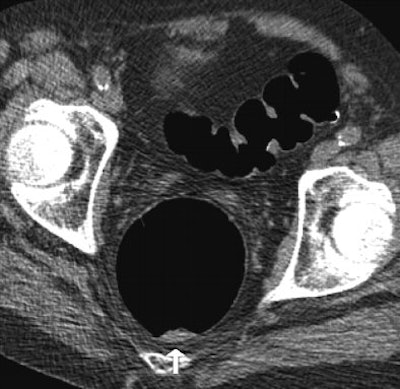

| Above: Supine image of rectum in a 64-year-old woman shows nontagged material 6 mm or greater with small hyperdense spot in dependent part of rectum (arrow). Hyperdense spot probably corresponds to some barium. Below: Prone view of rectum in the same patient shows nontagged fecal material has moved to anterior rectal wall (arrow). Image shows nontagged feces 6 mm or larger in rectum, possibly caused by remnants of bisacodyl suppository. P Lefere, S Gryspeerdt, J Marrannes, M Baekelandt, B Van Holsbeeck, "CT Colonography After Fecal Tagging with a Reduced Cathartic Cleansing and a Reduced Volume of Barium" (AJR 2005, 184: 1836-1842). |

Overall the researchers found residual feces in 413 segments (34.41%), including fecal material smaller than 6 mm in 210 segments (17.5%) and 6 mm or larger in 203 segments (16.92%). In addition, 527 segments contained residual fluid (43.91%), detected as it moved between prone and supine imaging. Nontagged feces 6 mm or greater were present in 49 segments (4.08%) and nontagged fluid in 178 segments (14.83%).

"The false positives were caused in four patients because of diverticulosis with severe luminal narrowing and thickening of the folds," Lefere and colleagues commented. In these cases, a differential diagnosis that included carcinoma was made. Only 4% of segments presented with untagged feces 6 mm or larger, and this result was limited to the presence of one fecal ball in more than two-thirds of these patients.